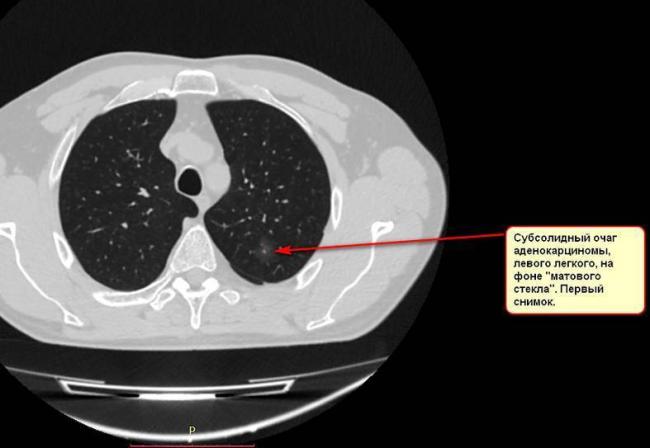

- В случае, когда образование представляет собой так называемое «облачко» или очаг по типу «матового стекла», требуется более предметное обследование. Внешне оно выглядит как затуманенная область с размытыми границами. В ряде стран пациентам с такими образованиями сразу рекомендуется операция, даже если оно не растет. Уже доказано, что в 80% случаев такие очаги являются предраковым состоянием легких. Альтернатива немедленной операции — постоянное наблюдение с контрольными снимками раз в полгода-год.